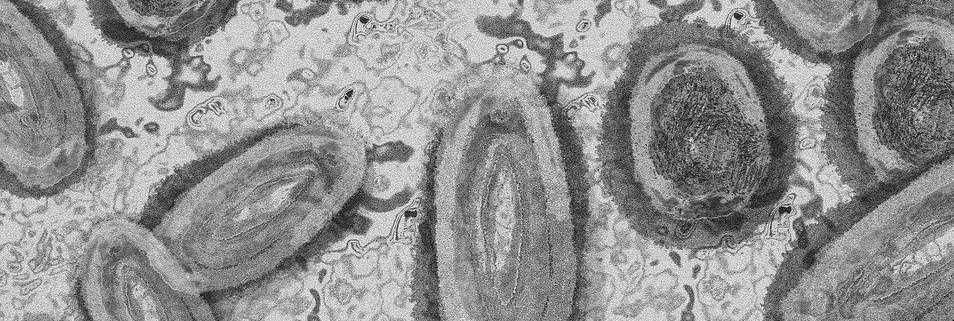

Els alumnes de primer de batxillerat de ciències de la salut han participat en el projecte Swi Micromon. Aquest projecte consistia en treballar l'amenaça de la resistència als antibiòtics buscant uns nous bacteris resistents i així motivar als estudiants en les ciències A més, van participar el professorat de l'institut al costat del professorat de la universitat amb els seus alumnes. El projecte es va realitzar en cinc sessions dirigides pels alumnes del professorat de la universitat, supervisats pel mateix professorat

En la primera sessió els van explicar en què consistia el projecte, els alumnes de l'IES Benicalap es van agrupar en parelles i els van donar el material adequat per a començar Primer havien de recollir mostres de terra del sòl, cada parella en una zona diferent per a tindre més probabilitats de trobar l'objectiu del projecte, bacteris resistents. A més, havien de recollir les coordenades exactes amb les característiques de la terra per a recopilar tota la informació amb més exactitud

Els alumnes van portar les mostres recollides a la segona sessió on els alumnes de la universitat els van explicar la mateixa sessió. El material utilitzat en aquesta sessió van ser un tub amb la mostra del sòl, tres plaques Petri iguals, cinc tubs estèrils plens de solució salina estèril, cinc pipetes Pasteur estèrils i una ansa Digralsky estèril També van utilitzar la protecció necessària per a no infectar­se i van començar. Van deure durant dues sessions (aquesta i la següent) aïllar els bacteris mitjançant processos de laboratori Per a això, van

realitzar quatre dissolucions de solució salina estèril juntament amb la mostra de la terra i ho van estendre en l'agar de les plaques Petri Després les van incubar a temperatura ambient durant uns dies Ho van realitzar així, perquè, en la següent sessió que seria la tercera, aparegueren colònies visiblement diferents. Van calcular el número d'aquestes i van haver de passar 20 colònies diferents de totes les que van trobar a una nova placa ordenadament on aquesta va ser incubada, al seu torn, van apuntar les característiques de cada colònia

En la sessió quatre van tornar a sembrar aquestes colònies diferents en dues noves plaques de cultiu pur per a incubar­la a 30 graus durant 48 hores Això ho van fer per a veure l'activitat de les colònies enfront de microorganismes de rellevància clínica que contenien les noves plaques. Després de tot això, el projecte arriba a la seua fi en la cinquena sessió. La sessió va consistir en observar que microorganismes van produir antibiosis en alguna de les plaques Afortunadament molts alumnes van trobar activitat en les colònies El que van trobar ho van portar a la universitat perquè ho analitzaran.

Tant tots els alumnes com el professorat van quedar molt satisfets amb el projecte Van mentalitzar als alumnes sobre la resistència microbiana i les seues conseqüències que pot haver­hi en un futur per un mal ús d'antibiòtics A més, a cada alumne se li va atorgar el seu diploma en agraïment a la seua participació.